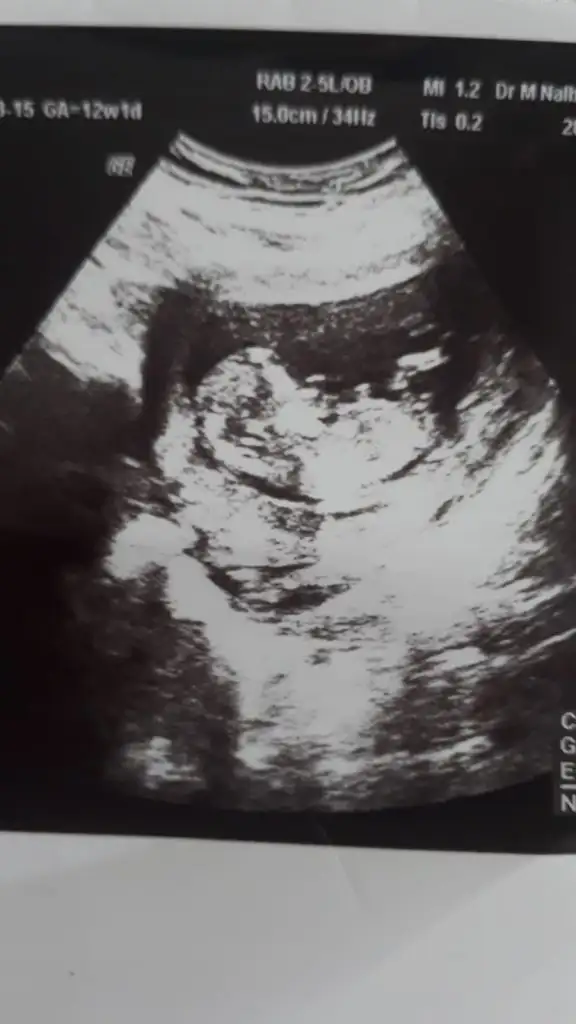

05QHazal Guru Kayıtlı Üye 24 Aralık 2012 606 234 323 23 Ağustos 2020 Konu Sahibi Konu Sahibi VeNi #41 tahminlerinizi alabilirmiyim Eklentiler IMG-20200823-WA0004.webp 18 KB · Görüntüleme: 43